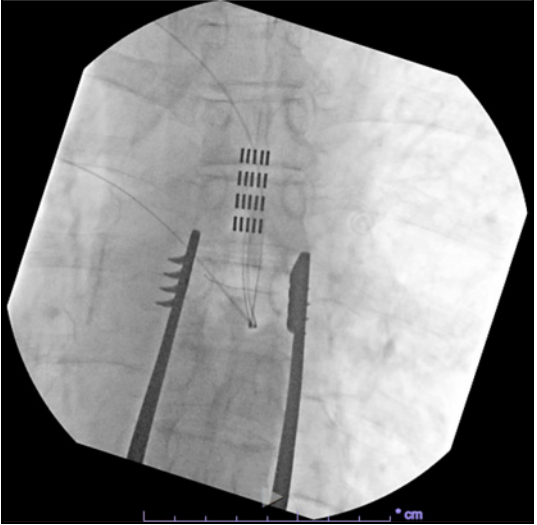

经疼痛科行SCS临时电极测试,于T7椎体上缘植入2根8触点针状电极,刺激后疼痛缓解90%,VAS降至1-3/10,遂决定行永久植入。通过T8椎板切开术,在T7中段至T7上段水平植入5根4触点针状电极,永久刺激器埋在腰部。初始设置为:脉宽500μs及1000μs,频率40Hz,电流1.7mA。

电极植入位置